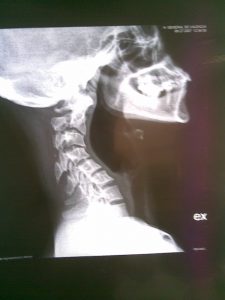

Cifosis postquirúrgica en RX dinámicas. En algunos casos existe dificultad para mantener la mirada al frente: como puede observarse en la segunda imagen. La extensión forzada de manera continua agota la musculatura y genera dolor e incapacidad, más evidente al final del día.